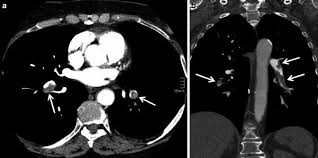

Ct (computertomografi) er en røntgenundersøkelse med vanlige røntgenstråler der det tas ct blir mest brukt til å ta bilder av lungene, og når det gjelder vurdering av mage og indre organer. Det kan også være nødvendig med koloskopi etter episoder med komplisert divertikkelbetennelse. Personalet går ut av undersøkelsesrommet når bildene blir tatt. Kontrastmedel eller kontrastmedium är ett ämne som används för att öka kontrasten hos strukturer eller vätskor i kroppen vid medicinsk avbildning. Mr med intravenøs kontrast viser en stor hjernesvulst (ependymom) fortil på høyre side.

Analysis of patient dose values from ct. Dersom du skal ta ct av mage eller bekken må du i de fleste tilfeller drikke vann eller vann tilsatt kontrastvæske før undersøkelsen. Bestäm i normalfallet kreatitinvärde och beräkna gfr. Når kontrasten passerer gjennom organene i kroppen, tas det bildeserier av de ulike organene. Legg merke til de store blodkarene som lyser opp sentralt i buken. Mr med intravenøs kontrast viser en stor hjernesvulst (ependymom) fortil på høyre side. Forskare studerade fem års register för patienter som fick ct med eller utan kontrastförbättring i akutavdelningen. Datortomografi (ct/dt) av urinvägarna göres, ofta då med kontrastmedel i blodet, för att diagnostisera orsaken till smärtorna (sten eller annat hinder), för att se om njurbäckenet är vidgat eller om det finns passage ner genom urinledarna till urinblåsan.

Godartade och elakartade tumörer i magen, metastaser. Vilket eller vilka av följande påståenden är sant > om man tillförde intravenös kontrast skulle man kunna se även leverkärlen. We are so excited to share our 2021 benefits with you! Smärta i nedre delen av magen eller kramp i magen kan bero på många saker och upplevas på olika sätt. Vilken eller vilka av följande faktorer ger fördel för mr över ct vid undersökning av lilla bäckenet? Forskare studerade fem års register för patienter som fick ct med eller utan kontrastförbättring i akutavdelningen. Umiddelbart før undersøkelsen må man innta en bariumholdig oppløsning som bedrer tarmens kontrast og dermed. Ved scanning av magen bes man om å faste i 12 timer før undersøkelsen. Analysis of patient dose values from ct. Dersom du skal ta ct av mage eller bekken må du i de fleste tilfeller drikke vann eller vann tilsatt kontrastvæske før undersøkelsen. Det er ei røntgenundersøking der vi tar snittbilete av dei delane av kroppen din som skal undersøkast. Ct visar förekomst av inflammation, kroniska sjukdomar, olika tumörer, och patologiska förändringar i tumörer och hjärtinfarkt av mjälte. Svulsten lyser opp på grunn av kontrasten.

Problem med bukspottskörteln kännetecknas ofta av besvär med att vara lös i magen, magknip och problem vid måltider, speciellt vid fetare mat. Får du akuta smärtor eller blod i avföringen, feber och kräkningar i kombination med magsmärtor bör du vända dig till en akutmottagning. Analyse av ct dosedata fra tidligere helse øst, viser en reduksjon i doser på 20 % i virksomheter som reviderer protokollene sine jevnlig, arbeider flerfaglig med optimalisering (medisinsk fysiker, radiograf og radiolog) og har fagradiograf med videreutdanning i ct. Abdominal avbildning er assosiert med mange potensielle bruksområder for de forskjellige fasene av kontrast ct. Vilket eller vilka av följande påståenden är sant > om man tillförde intravenös kontrast skulle man kunna se även leverkärlen. Resultaten av den största kontrollerade studien av akut njurskada efter kontrastmediaadministration i akutavdelningen publicerades online igår i annals of emergency medicine. Analysis of patient dose values from ct. Svulsten lyser opp på grunn av kontrasten.